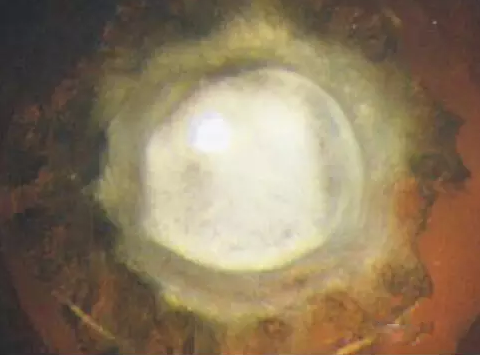

上图所示成熟期白内障,可见晶状体为完全的乳白色混浊,相应视力严重下降,它是白内障发展到成熟阶段的表现。其不具特异性,常可发生于视网膜脱离、外伤、葡萄膜炎、糖尿病等疾病。手术摘除是治疗成熟期白内障的最好方法,此外手术还可降低眼压。